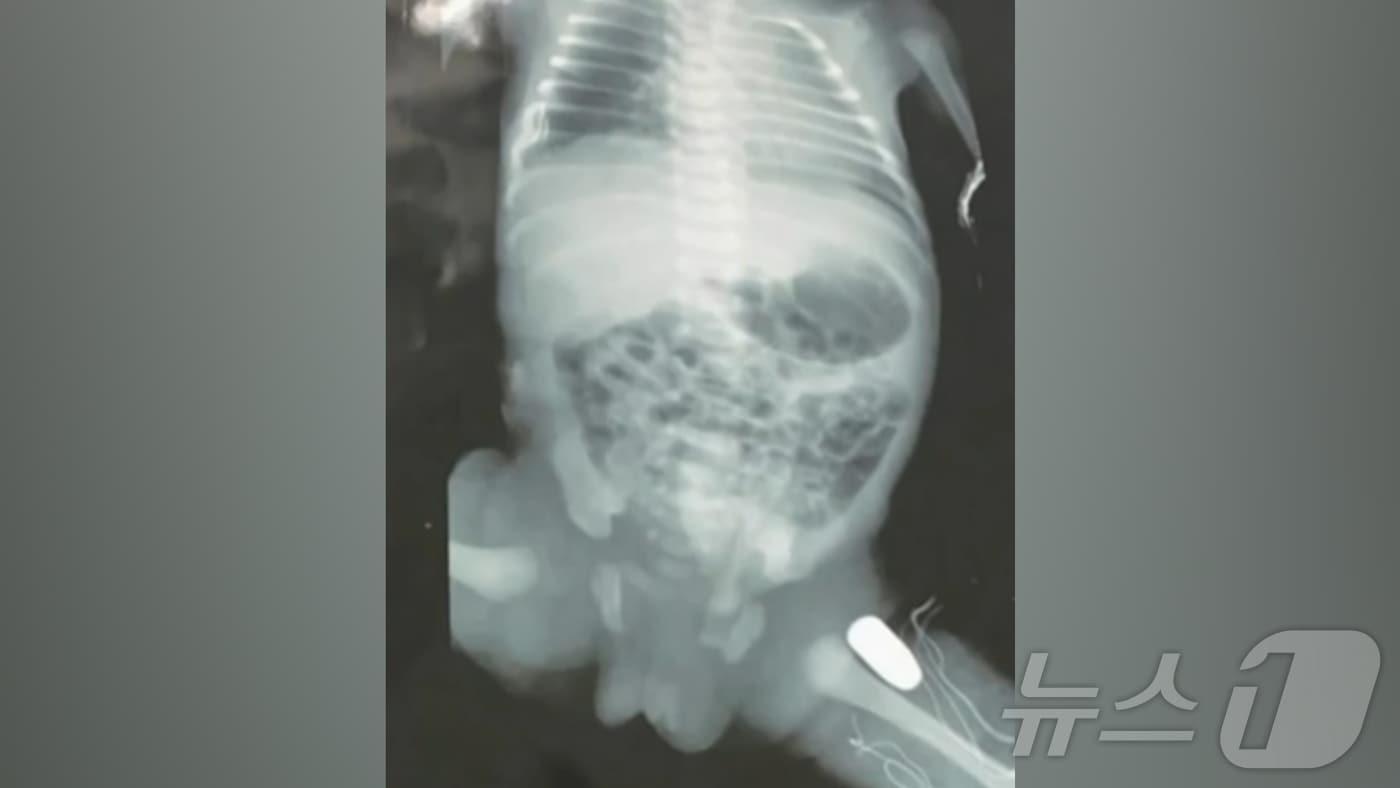

브라질에서 지난 16일(현지시간) 임신 32주째인 임산부가 총격당해 태아의 다리에 총알이 박혔으나 산모와 태아 모두 가까스로 생명을 구하는 기적 같은 일이 발생했다.(CNN 브라질 갈무리).